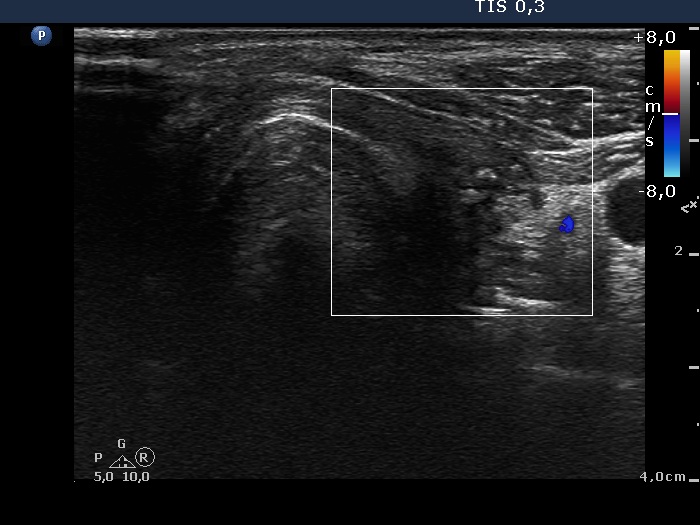

Right lobe, longitudinal scan

Left thyroid, transverse scan, color Doppler mode. There is no vascularization in the thyroid bed.